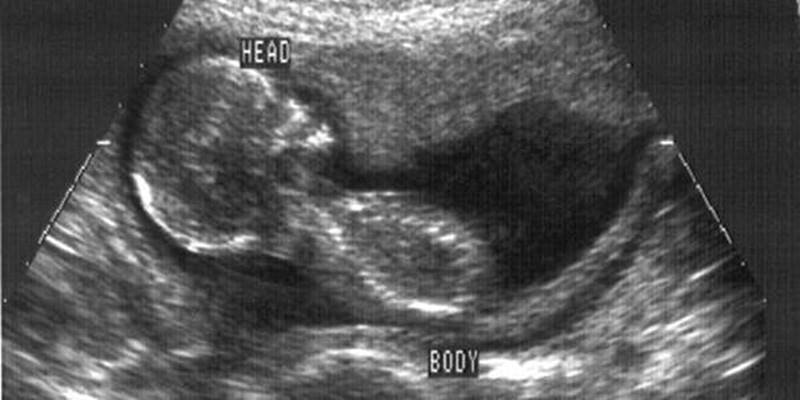

Фото из открытых источников